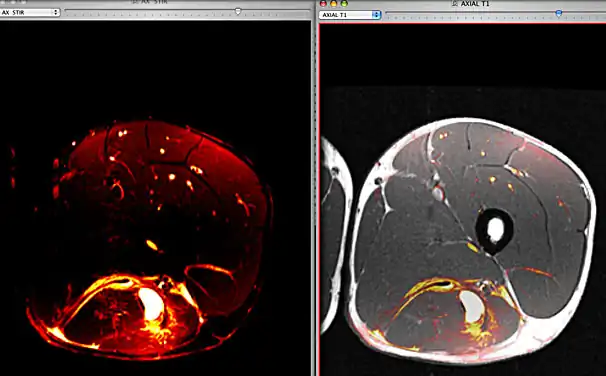

Fusion image between axial STIR and T1 images of a football player with a hamstring hematoma. These images were performed during the same imaging exam and were automatically aligned by OsiriX.